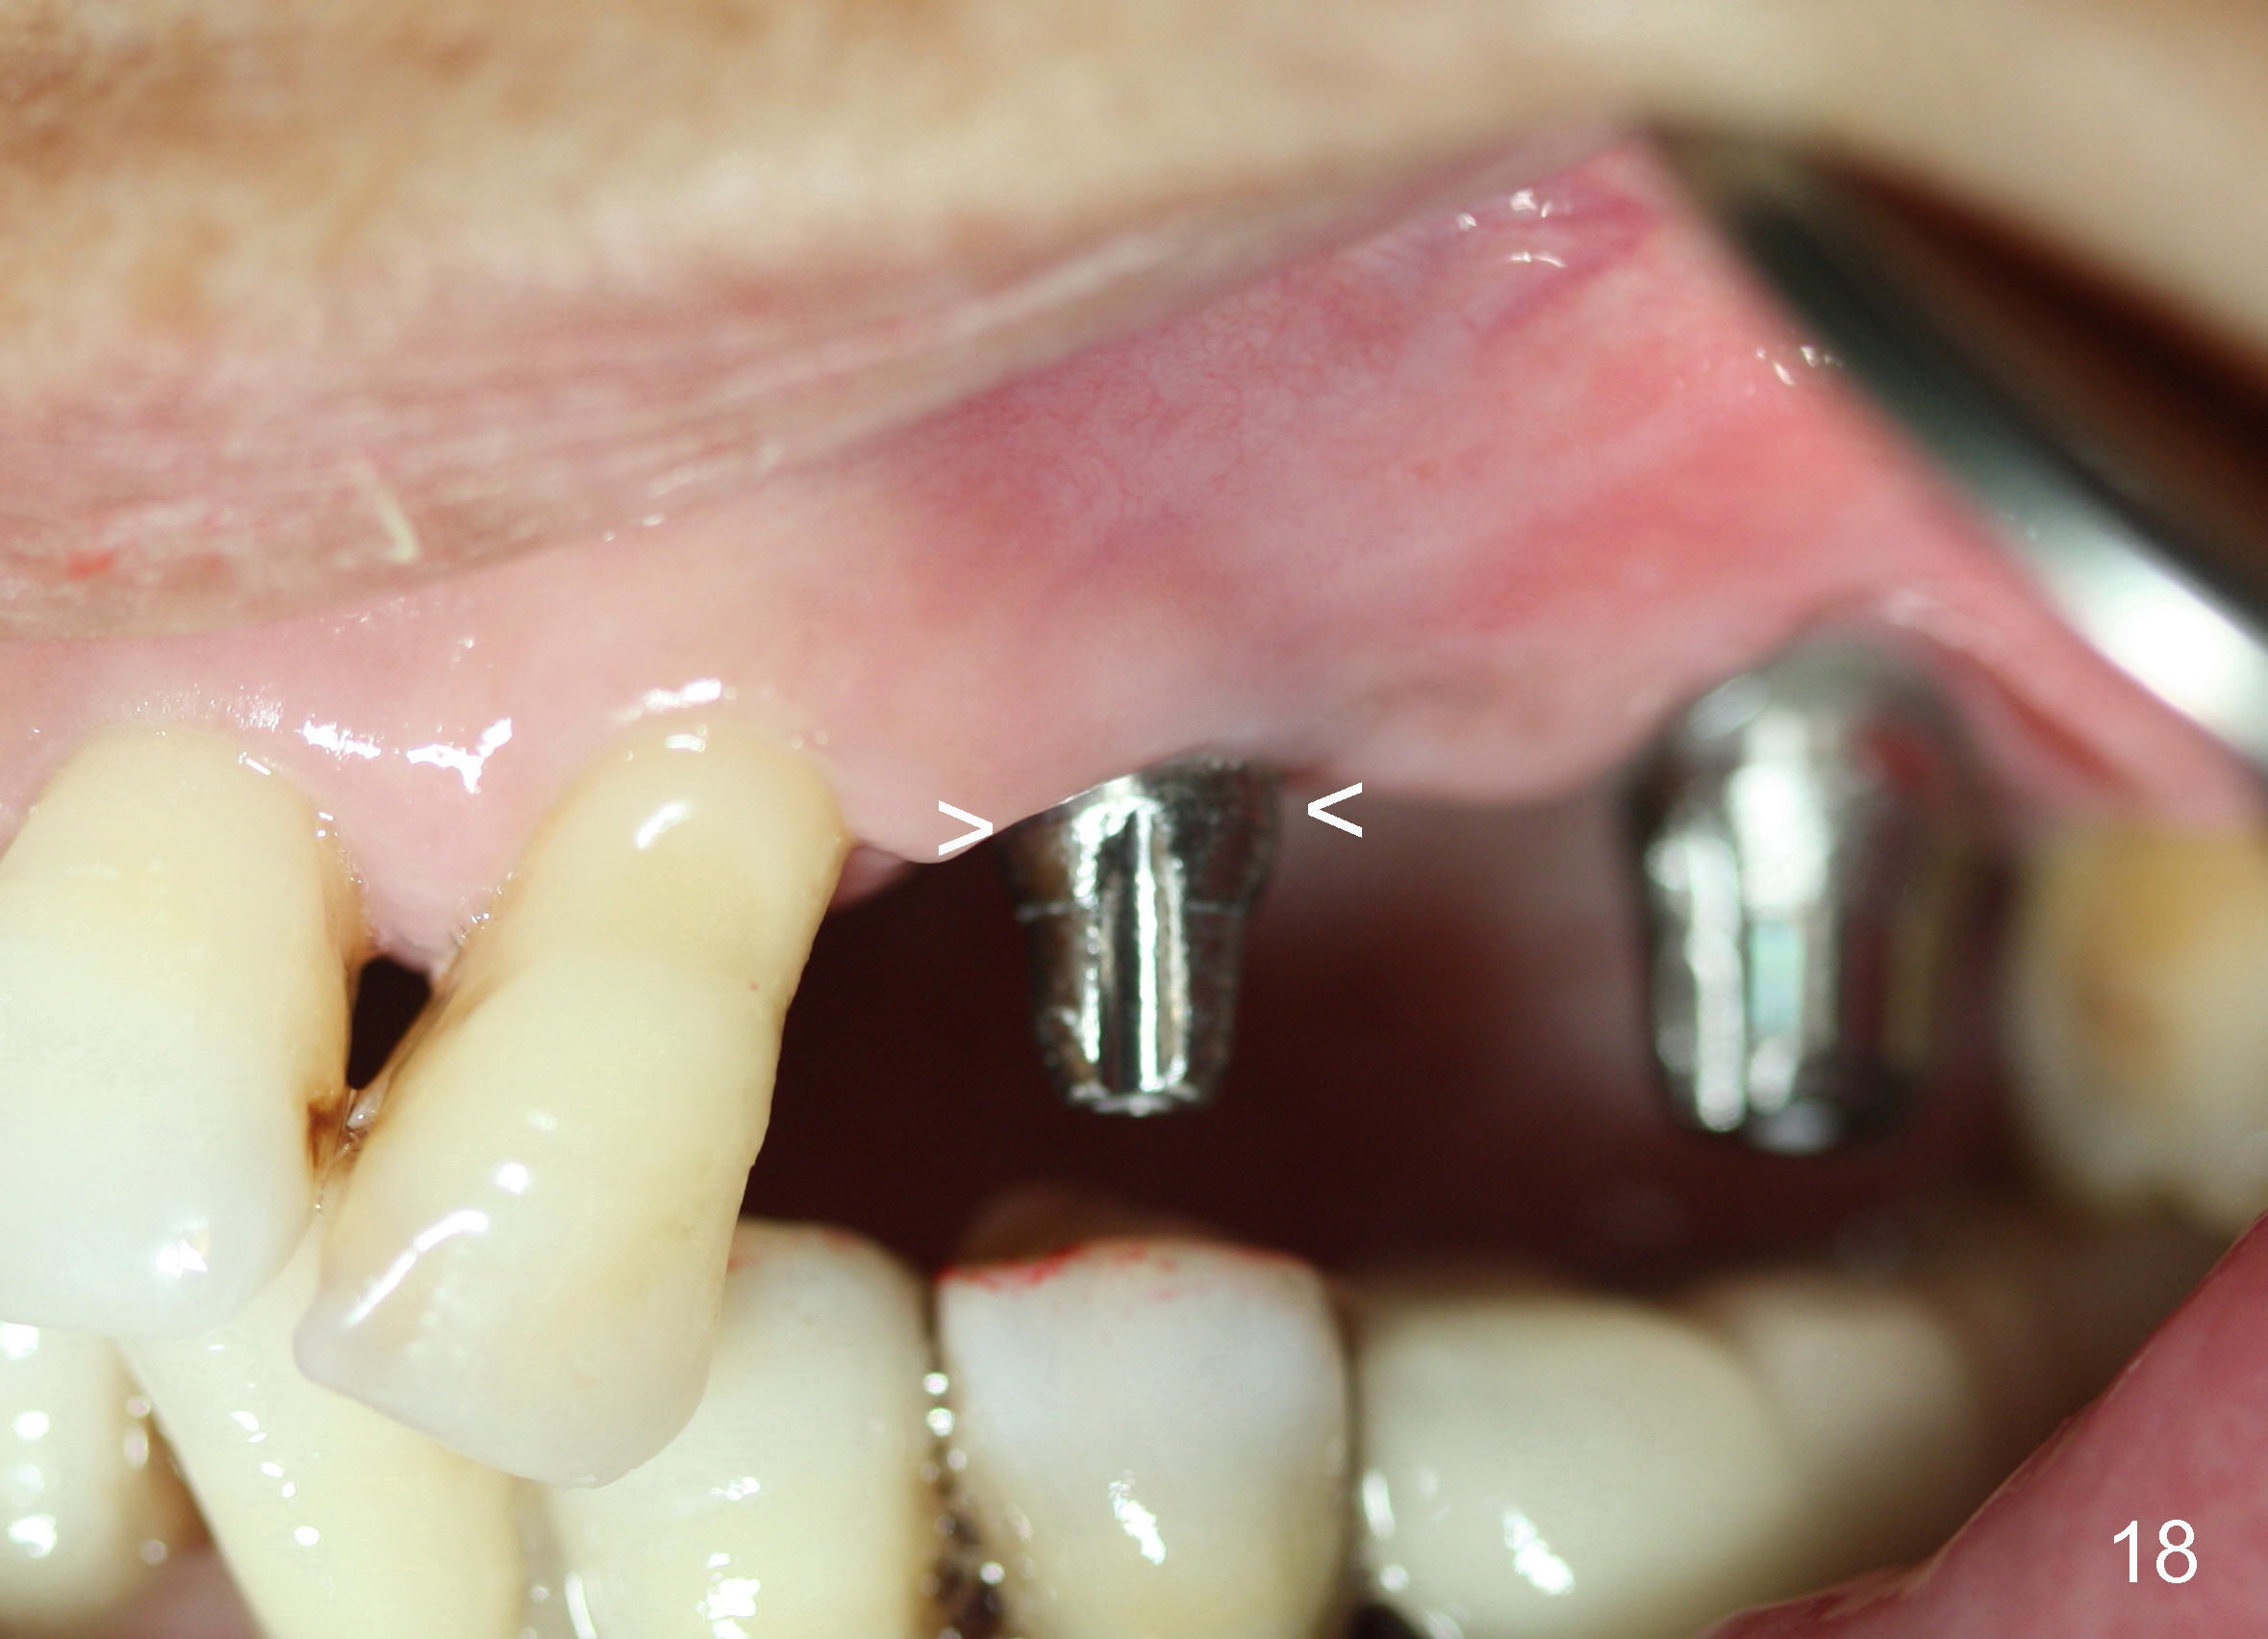

Two PAs are taken 5 months postop (Fig.15,16). Patterns of bone graft (*) between these PAs are different, which suggests presence of the graft buccal to the implant at the site of #14. Another piece of evidence of the graft is that the buccal socket heals (Fig.17 B) without implant thread exposure (Fig.19). These two implants are ready for definitive restoration (Fig.18-20). Fig.21 shows the final restoration 5 months post cementation.